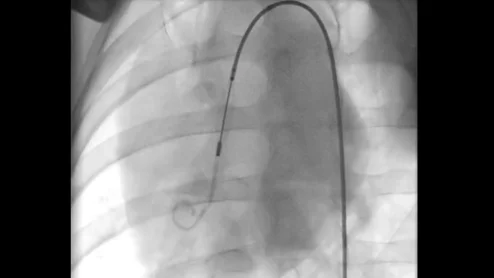

The system was developed to improve the complex, often time-consuming process of navigating through pulmonary arteries during embolectomy procedures.

Terry Bowers, MD, director of vascular medicine at Beaumont Hospital, Royal Oak, Michigan, and national co-chair of the Pulmonary Embolism Research Collaborative (PERC), explains the skillset needed for pulmonary embolism (PE) thrombectomy procedures. #PERT #PE